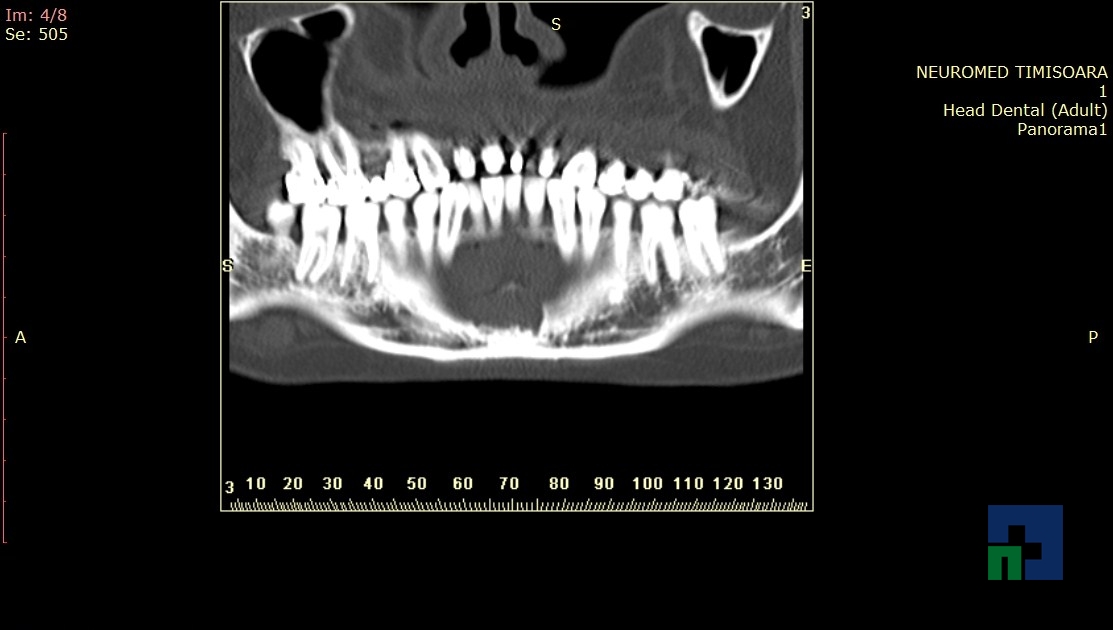

- Diagnosticul fracturilor:

-

- Unice

- Multiple

- Cu înfundare

- Complexe cranio-sinusale

- Complexe cranio-etmoidale

- Complexe cranio-orbitare

- Complexe cranio-faciale